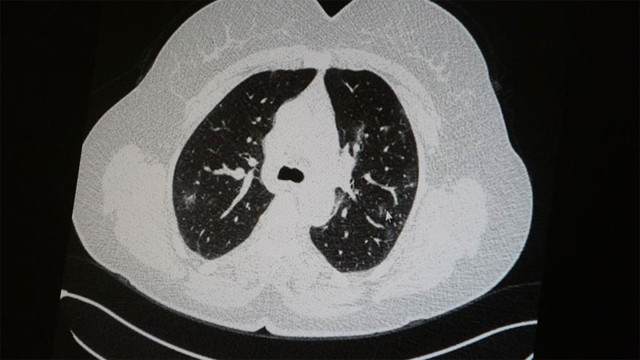

Genç olduğu halde aşı olmayanlarda hastalığın ağır seyrettiğini ifade eden Uzm. Dr. Azar, "Ben gencim, benim bağışıklık sistemim kuvvetli" diyen genç bir hastanın akciğerlerinde ciddi lekelenmelerin olduğunu ve korona virüs zatürresi olduğunu gördüklerini belirtti.